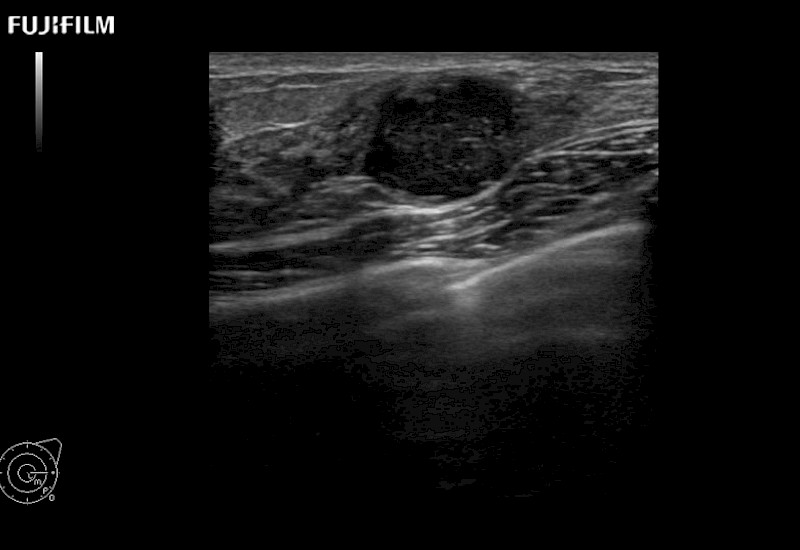

Extraordinary high-resolution digital imaging

Multi-Parametric imaging modalities

Our dedication to Surgical Oncology allows us to offer superior image quality, outstanding system reliability and intuitive use of cutting edge technology.

- Instant feedback on tumor margin delineation

- Valuable information to guide tumor resections

- Instant feedback on tumor margin delineation

- Instant feedback on tumor margin delineation